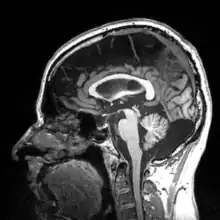

More recently, computed tomography has played a large role in reconstructing endocasts. The procedure is non-invasive and has the advantage of being able to analyze a fossil in record time with little risk of damaging the fossil under review. CT imaging is achieved through the application of x-rays to produce tomographs, or sectional density images, which are similar to the images produced during MRI scans.[8] CT scans use slices approximately 1 mm thick to reconstruct a virtual model of the specimen.[9] This method is especially useful when a fossil cranium is occupied by a natural endocast that cannot be removed without destroying the skeletal portions of the fossil. Because the cranium and its contents are of different densities, the endocranial cavity and its unique traits can be reconstructed virtually.[8]

Radiographic technique such as computed tomographic imaging, or CT scans, coupled with computer programming have been used to analyze brain endocasts from as early as 1906.[10] Recent development of advanced computer graphics technology have allowed scientists to more accurately analyze of brain endocasts. M. Vannier and G. Conroy of Washington University School of Medicine have developed a system that images and analyzes surface morphologies in 3D. Scientists are able to encode surface landmarks that allows them to analyze sulcal length, cortical asymmetries and volume.[11] Radiologist, paleoanthropologists, computer scientists in both the United States and Europe have collaborated to study such fossils using virtual techniques.[10]

Recent studies by Emiliano Bruner, Manuel Martin-Loechesb, Miguel Burgaletac, and Roberto Colomc have investigated the connection between midsagittal brain shape and mental speed. This study incorporated human subjects' cognitive testing in relationship to extinct humans. They used 2D from 102 MRI-scanned young adult human for comparison. Such correlations are small, suggesting that the influence of midsagittal brain geometry on individual cognitive performance is negligible but still provides useful information of evolutionary traits of the brain. Areas associated with the parietal cortex appear to be involved in relationships between brain geometry and mental speed.[18]